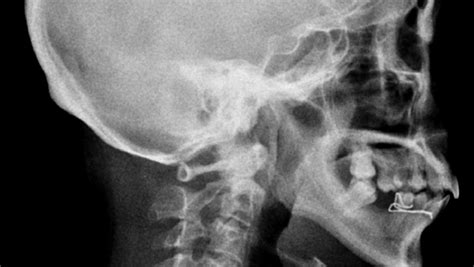

So, how is Arnold-Chiari I Malformation diagnosed, and what can be done about it? Diagnosis typically involves a neurological examination followed by an MRI of the brain and spinal cord. The MRI allows doctors to visualize the cerebellar tonsils and determine the extent of the herniation. In some cases, other tests, such as a CT scan or X-ray, may be used to rule out other conditions. Treatment options vary depending on the severity of the symptoms. For individuals with mild or no symptoms, observation and regular monitoring may be sufficient. However, for those with more severe symptoms, surgery may be necessary to relieve pressure on the brainstem and spinal cord. The most common surgical procedure is posterior fossa decompression, which involves removing a small portion of the bone at the back of the skull to create more space for the cerebellum. This surgery can help to alleviate symptoms and prevent further neurological damage. In some cases, other surgical procedures, such as a duraplasty (widening of the dura mater, the membrane that surrounds the brain and spinal cord), may be performed to further relieve pressure. It is important to note that surgery is not always successful in eliminating all symptoms of Arnold-Chiari I malformation. Some individuals may continue to experience mild symptoms even after surgery. However, surgery can often improve the quality of life for individuals with severe symptoms. In addition to surgery, other treatment options may include medications to manage pain, physical therapy to improve strength and coordination, and speech therapy to address speech and swallowing difficulties. A multidisciplinary approach involving neurologists, neurosurgeons, physical therapists, and speech therapists is often necessary to provide comprehensive care for individuals with Arnold-Chiari I malformation. It is important to discuss all treatment options with your healthcare provider to determine the best course of action for your specific situation. The decision to undergo surgery should be made in consultation with a neurosurgeon who has experience in treating Arnold-Chiari I malformation. Before undergoing surgery, it is important to understand the potential risks and benefits of the procedure. It is also important to have realistic expectations about the outcome of surgery. While surgery can often improve symptoms, it is not a cure for Arnold-Chiari I malformation. After surgery, it is important to follow your healthcare provider’s recommendations and attend all scheduled follow-up appointments. Regular monitoring is essential to ensure that your condition is stable and that you are receiving the most appropriate treatment. Living with Arnold-Chiari I malformation can be challenging, but with proper medical care and support, it is possible to manage the condition and maintain a good quality of life. Support groups and online forums can provide a valuable source of information and support for individuals with Arnold-Chiari I malformation and their families.